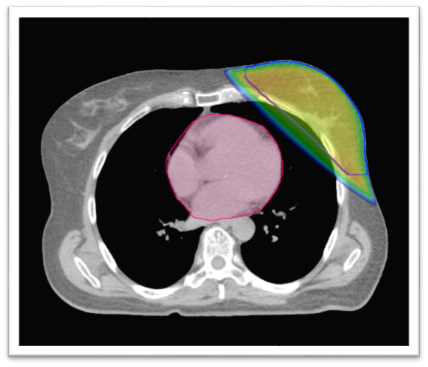

Radioterapie se připravuje pomocí CT vyšetření, na kterém je dobře vidět umístění srdce. Díky němu lze záření zacílit tak, aby procházelo jen prsem a srdce co nejvíce minulo (obr. 1). U většiny žen v případě použití moderních urychlovačů je dávka záření v oblasti srdce tak malá, že nepředstavuje žádné riziko. U menší části je ale srdce blízko u prsu a část záření jím prochází (obr. 2). V takovém případě lze použít ozařování v nádechu (obr. 3), pomocí kterého se srdce opět dostane do bezpečné vzdálenosti. A ozařuje se pouze v nádechu; urychlovač se tedy opakovaně vypíná a spouští. Nádech (polohu hrudníku) kontroluje speciální snímací zařízení položené na hrudníku.

Obr. 1: Srdce je vzdálené od prsu, nehrozí žádné riziko, standardní 3D technika radioterapie fotony lineárního urychlovače. Barevné linie v obrázcích: růžová barva – srdce; modrá linie – objem ozařovaného prsu; barevná plocha – ozářená oblast